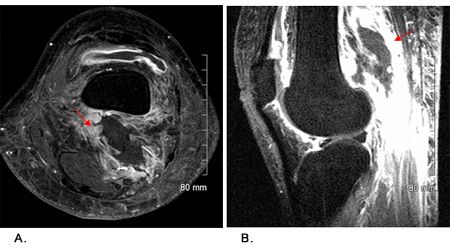

Arthrocentesis of the knee was performed to evaluate for septic arthritis or crystal arthropathy. There was blood in the aspirate and laboratory studies found 158,750 red blood cells, 150 nucleated cells, and no uric acid crystals. No organisms were found on Gram stain or culture. An MRI study of both knees showed extensive edema in the distal thigh and gastrocnemius muscles as well as in subcutaneous fat (Figure 1, A and B). Fluid was also seen at the short head of the left biceps femoris. The findings were consistent with diabetic myonecrosis (DMN).

DMN is a clinical diagnosis, although MRI can reveal extensive edema of the muscles and subcutaneous tissues. The diagnostic probability is increased in patients with type 2 diabetes mellitus who show no clinical signs of infection.2 Arthrocentesis with culture and analysis of the aspirate can help limit the differential. If a distinct fluid pocket can be isolated within the soft tissue, ultrasound- or CT-guided aspiration can help rule out an abscess or pyomyositis. Biopsy and surgery that requires debridement are not recommended because they prolong recovery time and increase recurrence rate.1Laboratory values are nonspecific; however, C-reactive protein and ESR may be elevated, with a normal creatine phosphokinase level.3